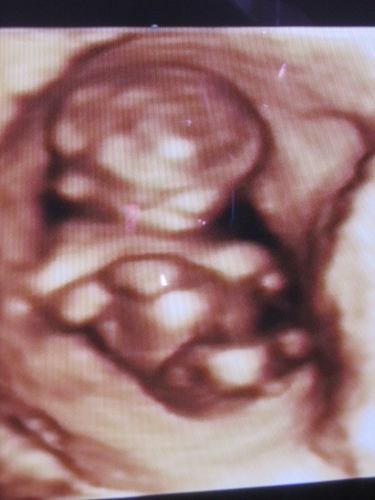

Kedden voltunk a kaáliba uh vizsgálaton, minden rendben van, így indulhat a kezelés!